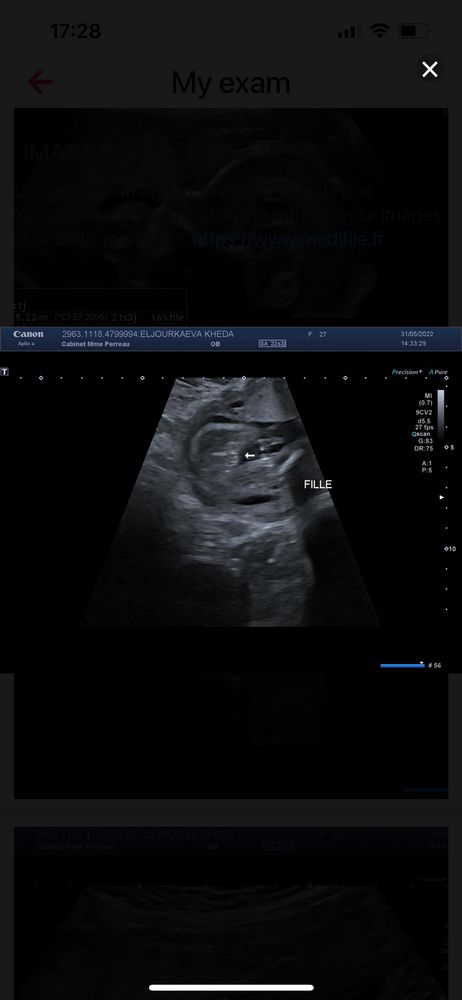

Говорит девочка, но как то странно))) где 2 полосы параллельные? Кофейное зёрнышко?

Нее это девочка

Был бы мальчик - было бы хорошо видно пенис и мошонку. Их нет, значит девочка. Полосок может и не быть видно.

Ну мошонки тут точно нет, так что выбор невелик!

Девчоночка ага.

Девочка❤️

Париж, если увеличить там видно кофейное зёрнышко